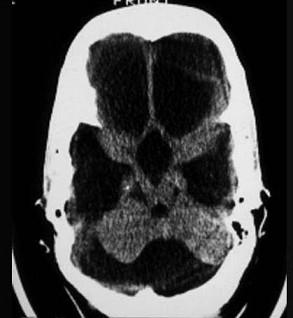

问题 根据CT表现考虑为 ( )

选项 A、大脑导水管狭窄 B、上矢状窦血栓形成 C、Arnold-Chiari畸形 D、颅底凹陷症 E、Dandy-Walker综合征

答案 E